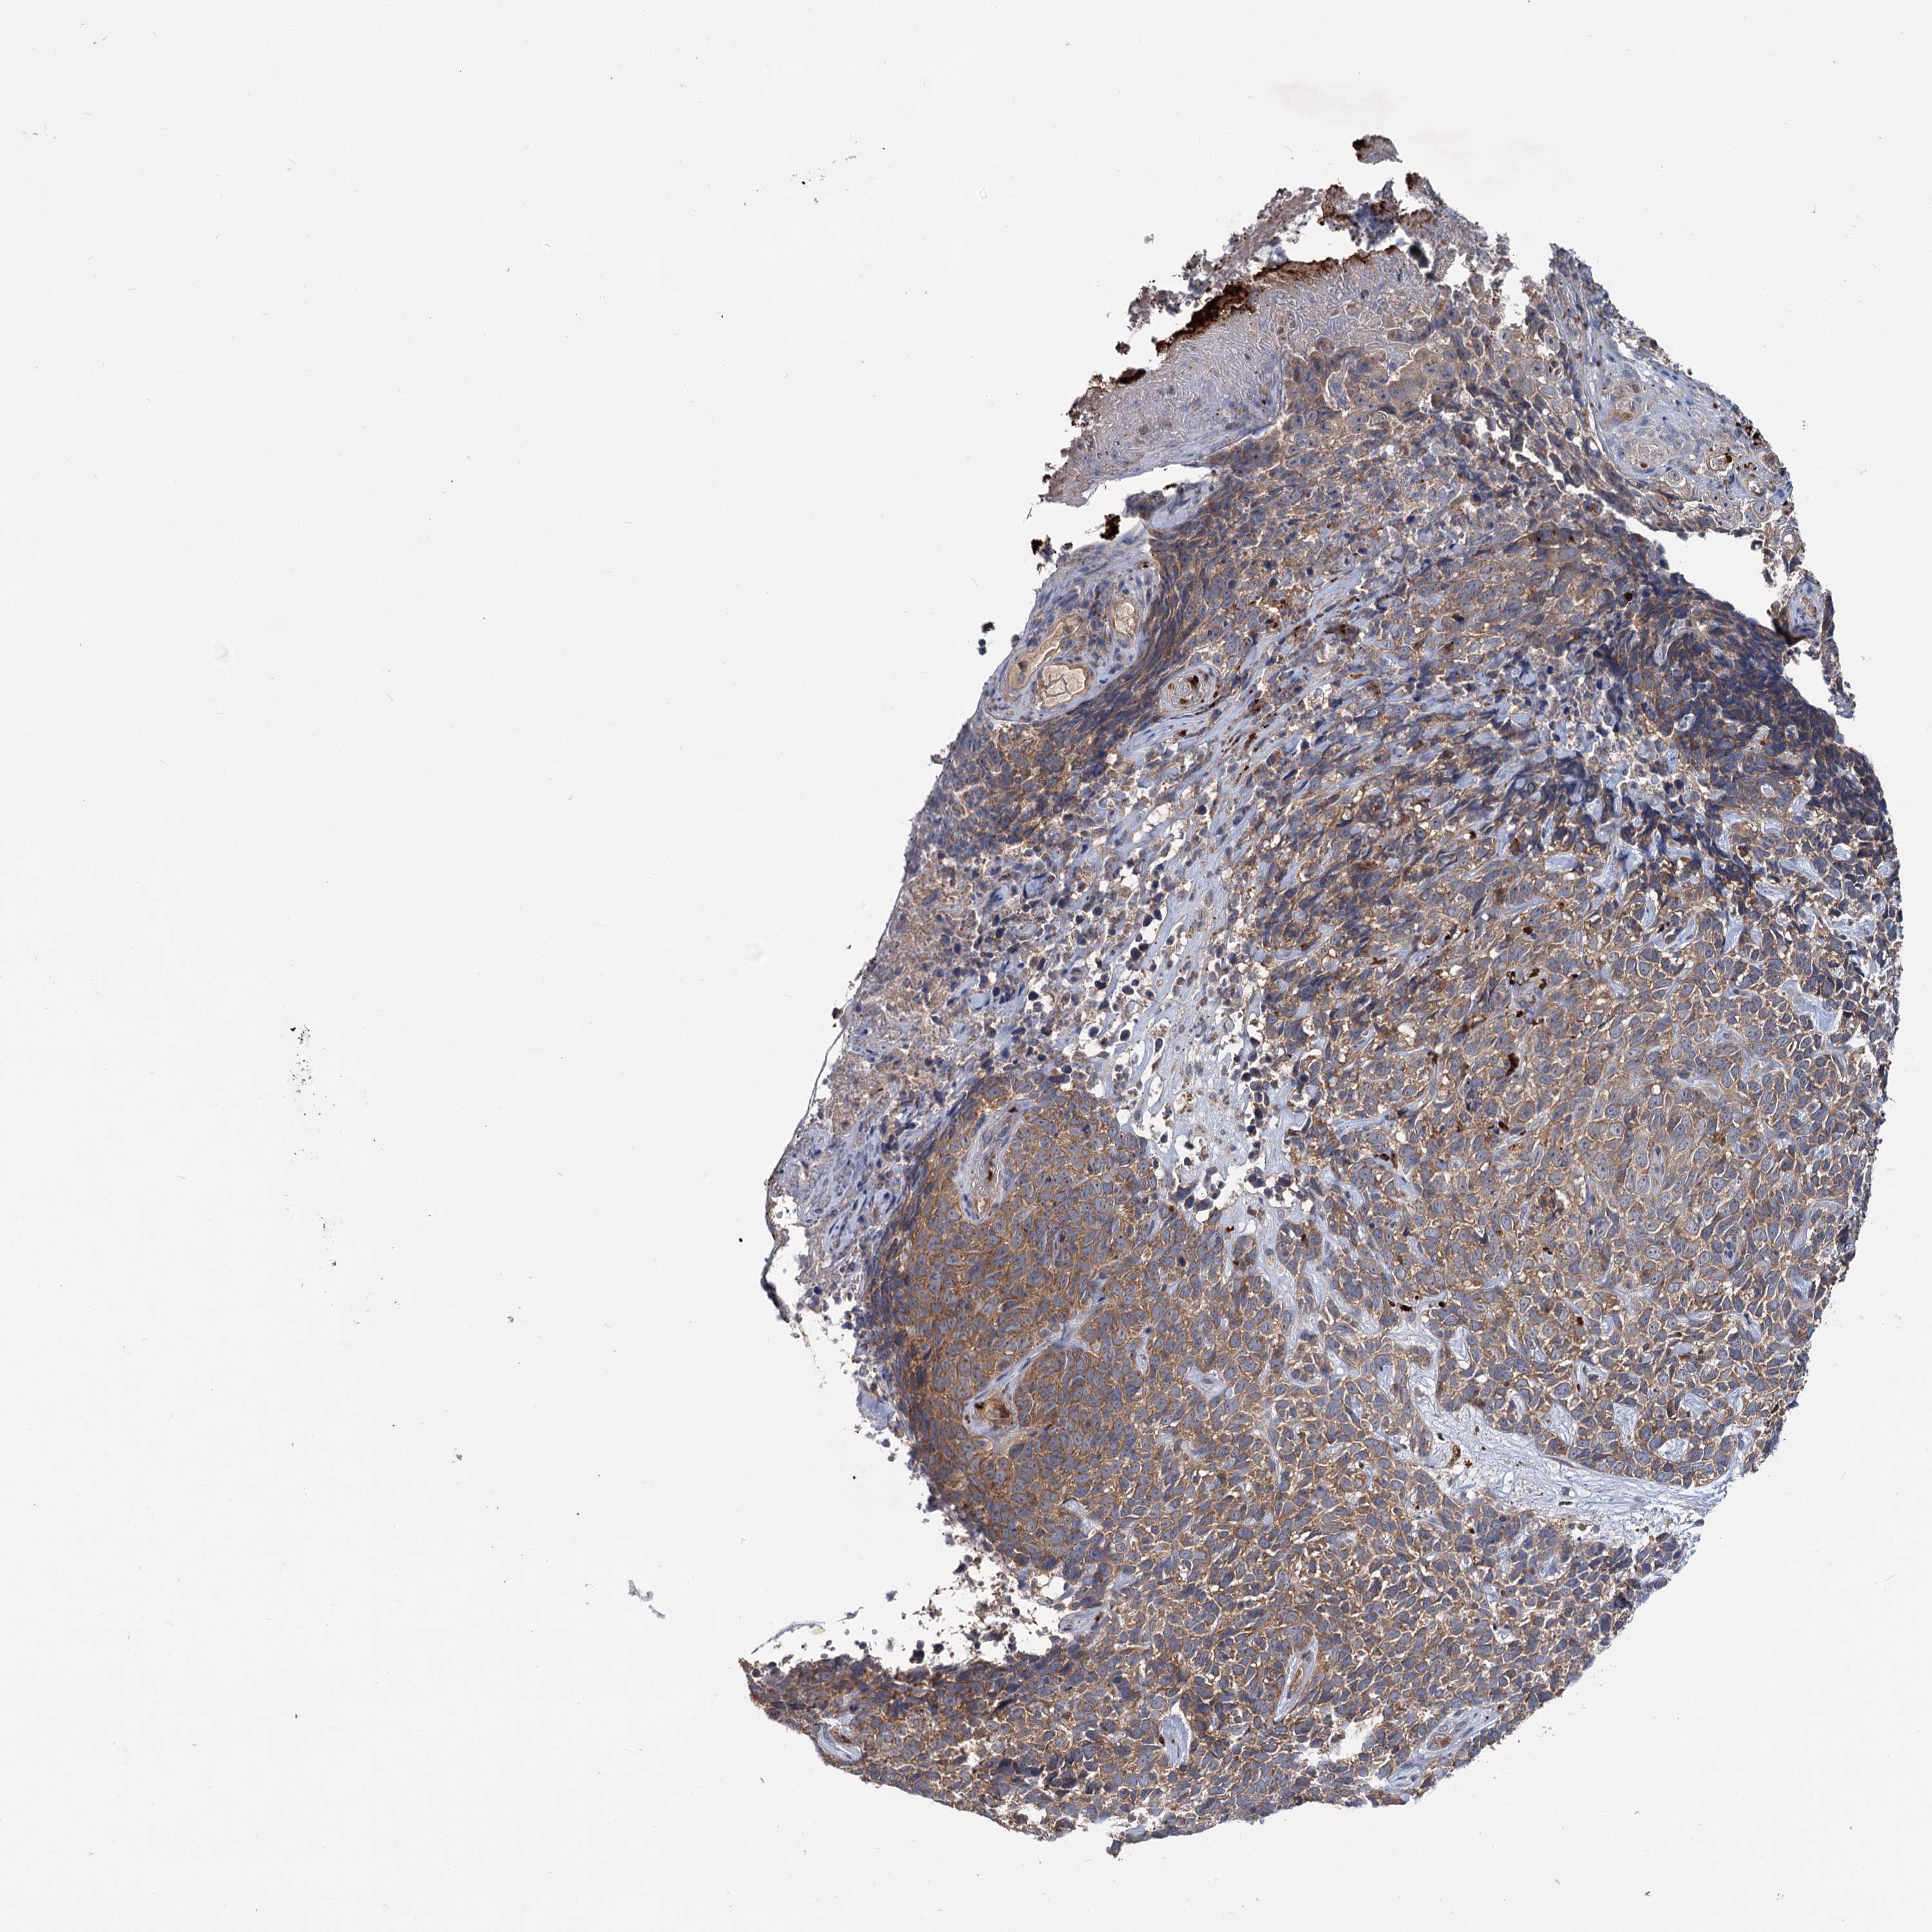

SKIN CANCER - Protein expressioni

A mouse-over function shows sample information and annotation data. Click on an image to view it in a full screen mode. Samples can be filtered based on level of antibody staining by selecting one or several of the following categories: high, medium, low and not detected. The assay and annotation is described here.

Antibody staining in the annotated cell types in the current human tissue is reported as not detected, low, medium, or high, based on conventional immunohistochemistry profiling in selected tissues. This score is based on the combination of the staining intensity and fraction of stained cells.

Each image is clickable and will lead to virtual microscopy that enables deeper exploration of all samples and also displays staining intensity scores, fraction scores and subcellular localization as well as patient and tissue information for each sample.

Antibody HPA039015

Basal cell carcinoma